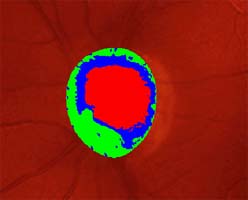

Modrá šipka - ukazuje plochu na sítnici, která obsahuje nervová vlákna. Sítnice je jemně proužkovaná, světlejší, cévy "jsou jako pod závojem". Červená šipka - ukazuje místo bez nervových vláken. Sítnice je tmavší, bez proužkování. Cévy jsou ohraničeny neobvykle ostře.